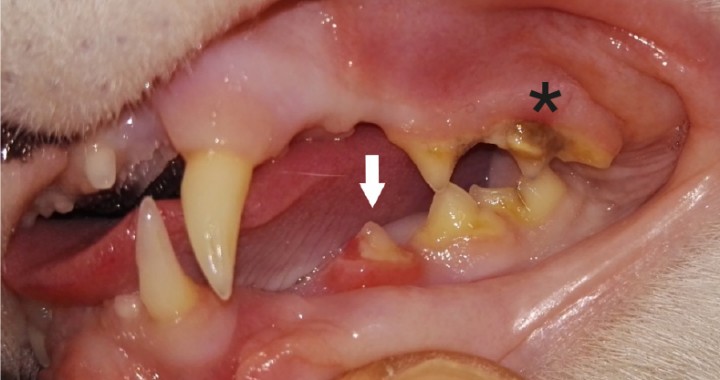

<p> Ausencia aparente de 106 (segundo premolar maxilar dere­cho) y 109 (primer molar maxilar derecho). Cálculo dental de índice 2 en 107 (asterisco). Gingivitis y sobrecrecimiento de la encía que cubre parcialmente el diente 407 compatible con RD (flecha).</p>

Ausencia aparente de 106 (segundo premolar maxilar dere­cho) y 109 (primer molar maxilar derecho). Cálculo dental de índice 2 en 107 (asterisco). Gingivitis y sobrecrecimiento de la encía que cubre parcialmente el diente 407 compatible con RD (flecha).

<p>Ausencia aparente de 206 (segundo premolar maxilar izquier­do) y 209 (primer molar maxilar izquierdo). Cálculo dental de índice 2 en 207 (asterisco). Gingivitis y sobrecrecimiento de la encía que cubre parcialmente el diente 307 compatible con RD (flecha).</p>

Ausencia aparente de 206 (segundo premolar maxilar izquier­do) y 209 (primer molar maxilar izquierdo). Cálculo dental de índice 2 en 207 (asterisco). Gingivitis y sobrecrecimiento de la encía que cubre parcialmente el diente 307 compatible con RD (flecha).